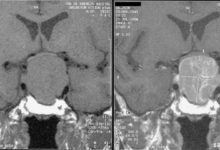

• Görüntüleme testleri: Ultrason ve bilgisayarlı tomografi de dahil olmak üzere görüntüleme testleri, doktorunuzun tiroidde anormal bir büyümenin olup olmadığını belirlemesine yardımcı olabilir.